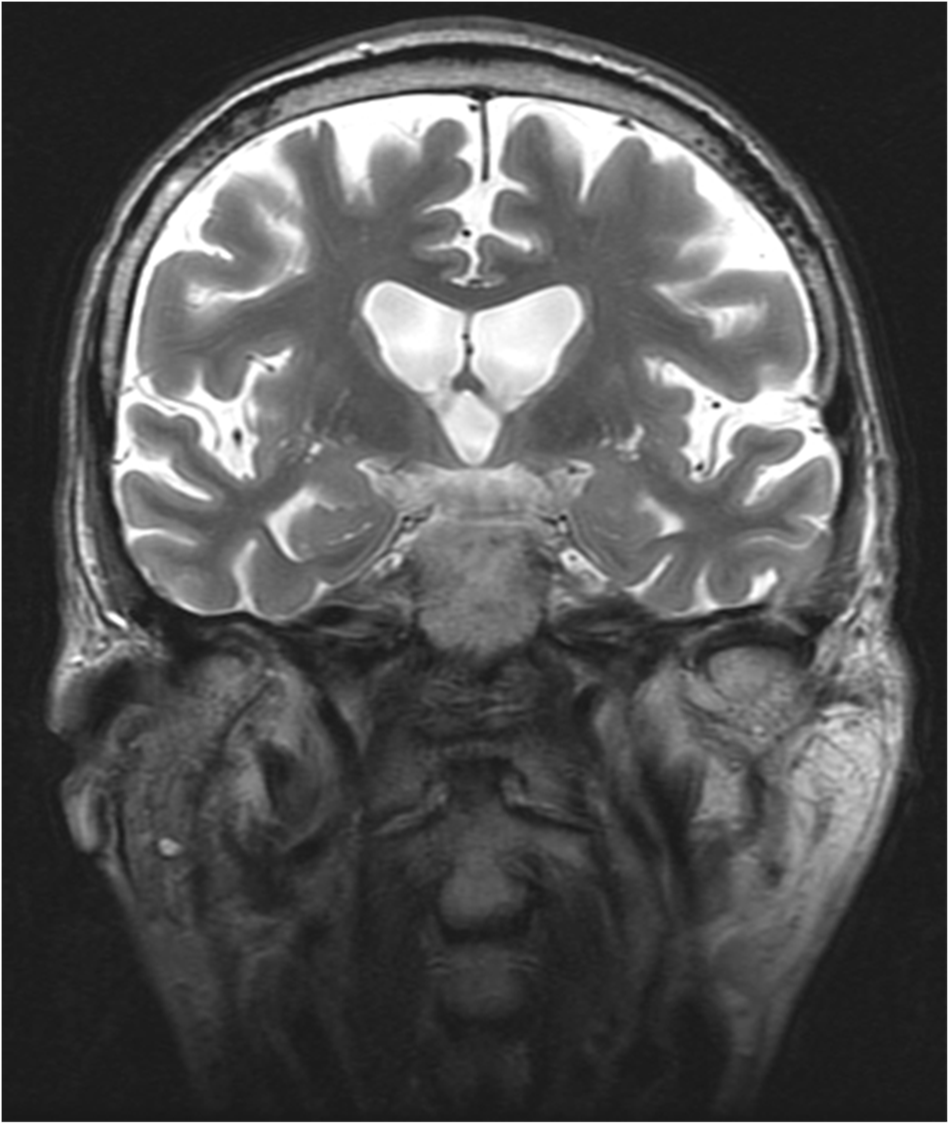

Popis jednotlivých částí

1. Corpus callosum

2. Nucleus caudatus

3. Septum pellucidum

4. Fornix

5. Globus pallidus

6. Putamen

7. Capsula interna

8. Thalamus

9. Plexus choroideus ventriculi tertii